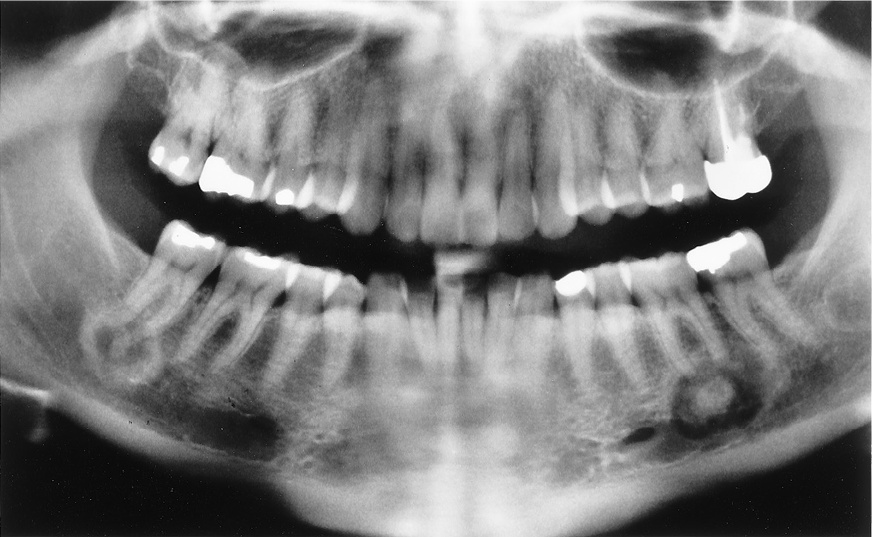

2 / 30

2. (Select ONE OR MORE correct answers)

The radiograph shows evidence of